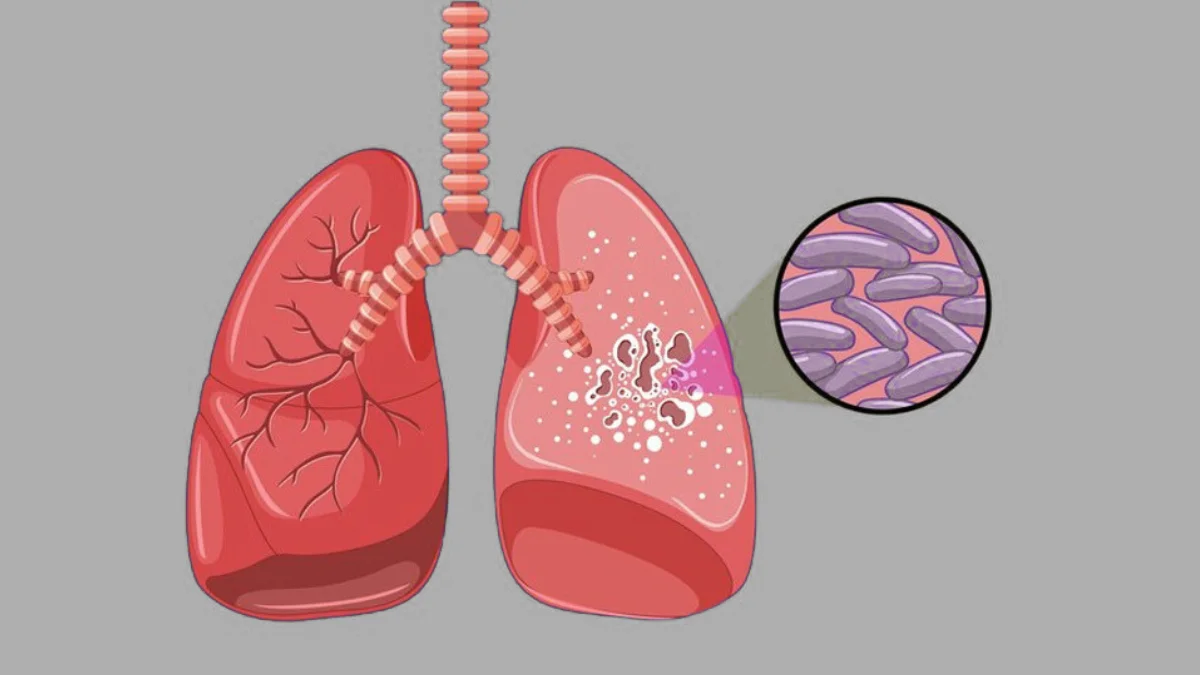

At Ekanshi Multispecialist Hospital, we provide advanced T.B. Treatment in Handewadi, Hadapsar, also known as tuberculosis care, to help patients recover safely and prevent complications. Tuberculosis is a contagious bacterial infection caused by Mycobacterium tuberculosis, primarily affecting the lungs but potentially spreading to other organs. It spreads through the air when an infected person coughs, sneezes, or talks. Symptoms of active TB include persistent cough, chest pain, fever, night sweats, weight loss, fatigue, and loss of appetite, while latent TB remains symptom-free but can become active if immunity weakens.

Moreover, timely diagnosis and strict adherence to treatment are essential to prevent drug-resistant TB. Treatment involves a supervised course of antibiotics lasting six months or more. Preventive measures such as the BCG vaccine, good cough hygiene, early detection, and avoiding close contact with active TB patients are crucial. With expert tuberculosis care, our hospital ensures effective recovery and reduces the risk of spread in the community.